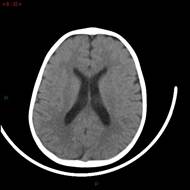

Se realiza RMN de cerebro. No se observan alteraciones. Se realiza tratamiento con imatinib 100 mg/día por 7 días sin respuesta (RAE: 7.440/mm3).